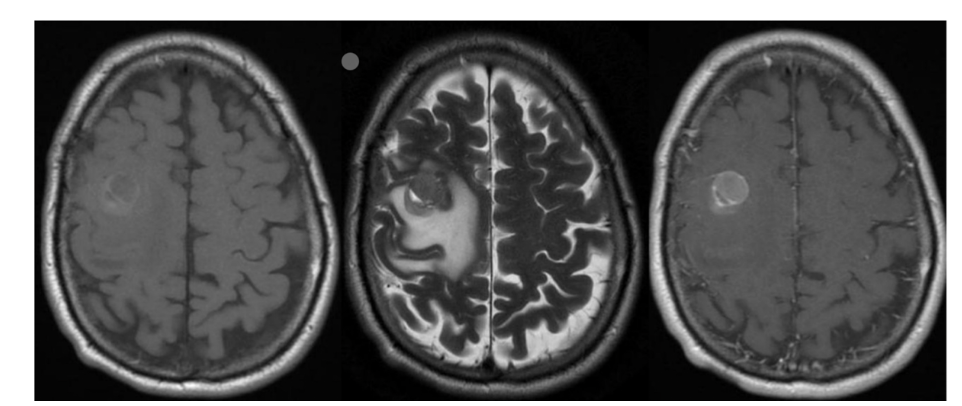

Sequences + Pathology?

• 1st = T1: the white matter is brighter than the grey matter

• 2nd = T2: the white matter is darker than the grey matter

• 3rd = T1 C+: still has T1 characteristics but there is vascular involvement as there is

increased signal from the lesion

• Path = intra-axial lesions